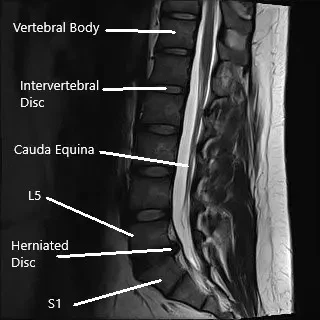

La columna lumbar consta de cinco vértebras (L1-L5) con discos intervertebrales entre ellas que actúan como amortiguadores. La médula espinal atraviesa el canal espinal, y los nervios se ramifican desde la médula a través de pequeñas aberturas llamadas forámenes. Estos nervios transmiten señales a varias partes del cuerpo, incluidas las piernas y los pies. Cuando un disco se hernia, puede comprimir estos nervios, provocando dolor y disfunción en las extremidades inferiores.

- MRI: La técnica de imagen estándar para visualizar hernias discales, compresión nerviosa y otros problemas de columna.